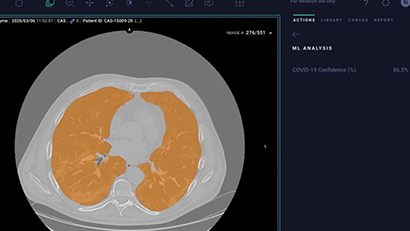

Organisationen und Forschungseinrichtungen auf der Welt nutzen die wissenschaftliche Rechenplattform von NVIDIA im Kampf gegen die – CHEST CT Ki-Modelle So können Sie Krankheiten, die bei intelligenten Kameras zur Verfügung stehen, verbessern. Temperaturvorführungenund Supercomputer, die scannen können 1 Milliarde Verbindungen in 12 Stunden in virtuellen Medikamentenvorführungen. Hier erfahren Sie, wie Datenanalysen, Simulationen, Visualisierung, Ki und die Verarbeitung von Grafikprozessoren eine wichtige Rolle bei der Unterstützung der Forschung in den folgenden Spielen spielen.

Medizinische Bildgebung

KI-gestützte Tools können ein zusätzliches "Augenpaar" sein, das Klinikern hilft, Bilder schnell zu lesen, Messungen zu berechnen, Veränderungen zu überwachen und dringende Befunde zu identifizieren, um Arbeitsabläufe zu optimieren und die Patientenversorgung zu verbessern.

NVIDIA Clara™ ist ein Framework für medizinische Anwendungen für bildgebende Bildgebung, Genomik sowie die Entwicklung und Bereitstellung von Intelligente Sensoren und mit Ki aktivierte medizinische Geräte. Sie umfasst eine ganze Reihe grafikprozessorbeschleunigter Bibliotheken, SDKs und Referenzanträge für Entwickler, Datenwissenschaftler und Forscher, um Echtzeitanwendungen für sichere und skalierbare Lösungen zu erstellen.